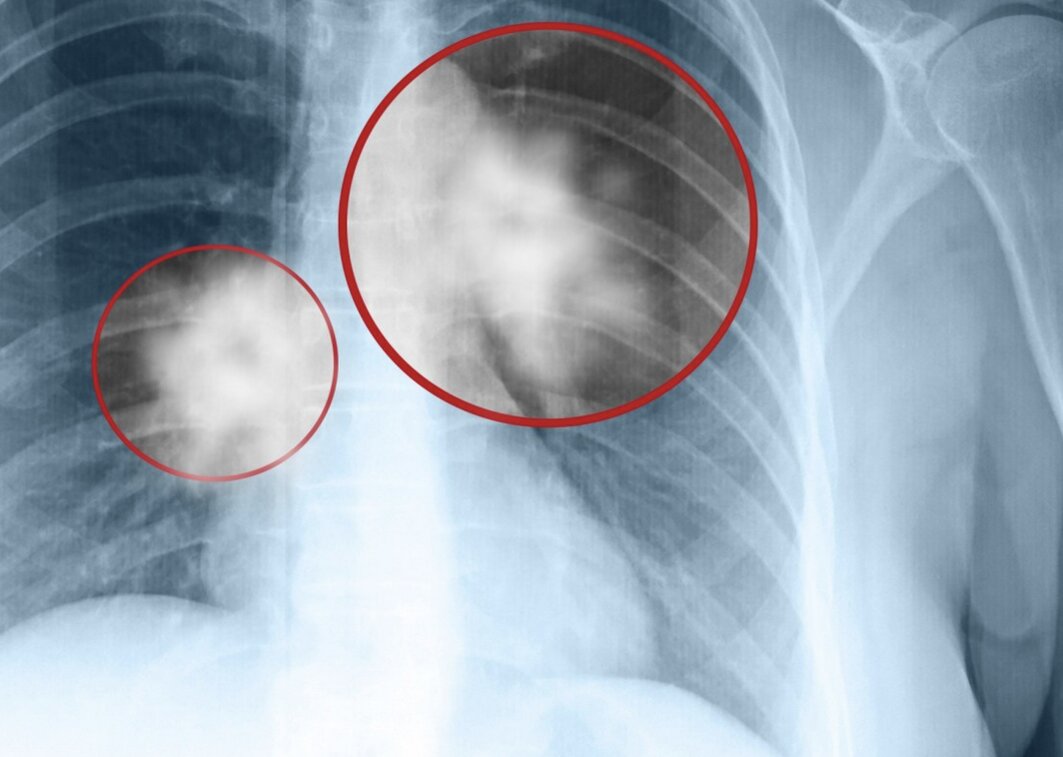

Mới đây, trang Sohu đưa tin, một câu chuyện gây chấn động y giới tại Trung Quốc: Một cặp vợ chồng lần lượt mắc ung thư phổi, khiến bác sĩ không khỏi đặt câu hỏi: "Gia đình này rốt cuộc đã trải qua điều gì?".

Theo thông tin từ bệnh viện, người vợ, một phụ nữ khoảng 60 tuổi, phát hiện khối u phổi kích thước 3cm khi đi chụp X-quang trong một lần khám sức khỏe tổng quát. Bà cho biết đã vô cùng bàng hoàng. Chồng bà đã qua đời vài năm trước vì ung thư phổi giai đoạn cuối, khi được phát hiện thì dịch phổi đã đầy, chỉ còn sống được một thời gian rất ngắn.

Nguyên nhân gây ung thư phổi của 2 vợ chồng: Người chồng nghiện thuốc lá nặng, thường xuyên hút trong nhà

Sau khi tìm hiểu, bác sĩ phát hiện nguyên nhân chính gây nên bi kịch này là do người chồng trước đó là người hút thuốc lá rất nặng, thường xuyên hút ngay trong nhà. Điều này khiến cả gia đình tiếp xúc với khói thuốc thụ động, dẫn đến nguy cơ mắc ung thư phổi rất cao.